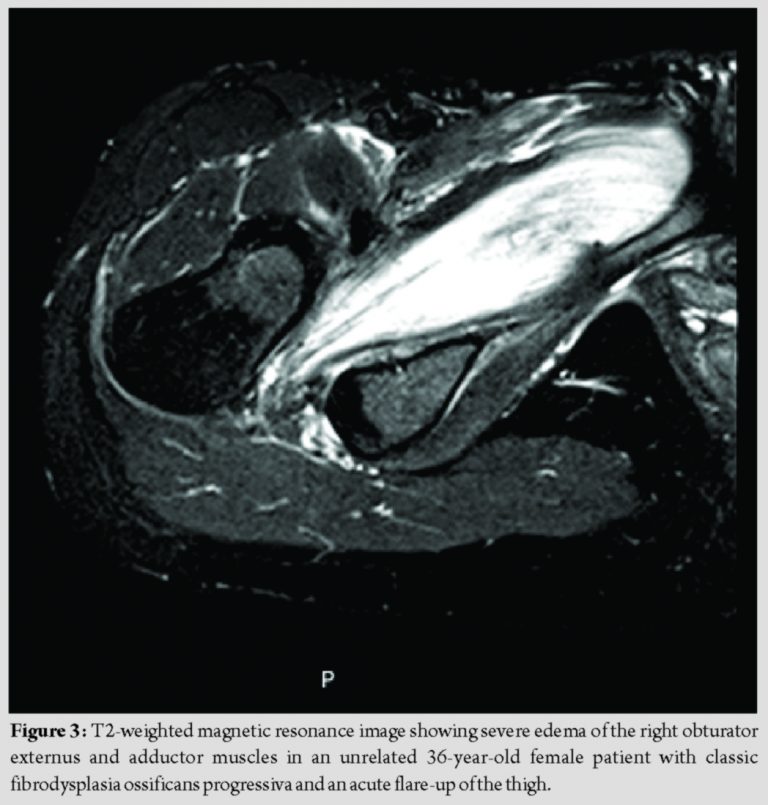

This unique case illustrates conclusively what has long been suspected – that intracompartmental pressures that dramatically exceed capillary filling pressure exist in an acute flare-up of FOP involving the thigh [15]. The normal pressure of a tissue compartment is between 0 and 8 mm of mercury. Capillary blood flow becomes compromised and severe pain may develop when tissue pressure increases to 30 mm of mercury. Muscle and nerve ischemia occur when tissue pressures approach diastolic pressure [16,17,18]. In the FOP patient reported here, the compartment pressure greatly exceeded the threshold for acute compartment syndrome.It is plausible that intracompartmental pressures were modulated by the extended period of treatment with corticosteroids and that rebound swelling and severe pain recurred when the corticosteroids were tapered and discontinued. This is the only case to our knowledge that specifically measured the pressure within a closed fascial compartment and documented an acute compartment syndrome during a flare-up of FOP. However, compartment syndrome may be more common than previously considered in painful appendicular flare-ups. Unfortunately, the diagnosis of FOP was probably unknown to the medical team who evaluated the patient in the emergency room [16]. It is difficult to determine the temporal emergence of the compartment syndrome as severe edema may occur throughout the evolution of an FOP flare-up. The early catabolic phase of an appendicular FOP lesion, regardless of whether it is induced by trauma or occurs spontaneously (as in our patient), is characterized clinically by increasing pain and histologically by extensive inflammation and extreme vascular permeability [1]. This early phase is often responsive symptomatically to a brief course of high-dose corticosteroids, but commonly subject to rebound edema with tapering or cessation of steroids [14]. The later anabolic phases of a symptomatic FOP lesion – specifically the transition from the fibrotic to the pre-osseous chondrogenic stage and eventually to the ossification stage – are often characterized by obstructive edema best seen on magnetic resonance imaging as the lesion increases in volume. In the very late stages of lesion formation, reactive edema may occur at the periphery of the lesion, where it is in contact with uninvolved tissue [19]. Thus, soft-tissue swelling and edema may occur throughout all stages of lesion evolution, lead to increased intracompartmental pressure that threatens the viability of the soft tissues within the compartment, precipitate cellular hypoxia of local tissues, amplify the BMP signaling pathway, and exacerbate the progression of heterotopic ossification [9,19]. It is unfortunate that the patient underwent intracompartmental pressure measurement and fasciotomy as invasive procedures such as these are contraindicated in FOP. However, many important lessons may be learned from this case, not the least of which is that FOP patients must make it abundantly clear to treating physicians that invasive procedures must be assiduously avoided. While emergency fasciotomy is the treatment of choice for acute compartment syndrome, the diagnosis of FOP is a contraindication to such a therapeutic maneuver, as the operative intervention will inevitably exacerbate the flare-up or be futile. It might be appropriate to consider non-operative approaches such as intravenous corticosteroids, although there is no evidence that such measures affect the outcome of acute flare-ups of FOP. Second, this unique case suggests that acute compartment syndrome exists during flare-ups of FOP, especially at appendicular sites, and may be more common than previously appreciated. The patient described here had a typical presentation for acute flare-ups involving the hip or thigh – with severe edema noted clinically at presentation. Her clinical picture is consistent with many FOP patients and similar to an unrelated FOP patient shown here where T2-weighted images on magnetic resonance imaging showed severe edema of the obturator externus and adductor muscles during an acute flare-up of FOP (Fig. 3) [20]. Third, the presence of severe swelling and resultant tissue hypoxia in a closed fascial compartment will release endogenous damage-associated molecular patterns, stimulate endogenous toll-like receptors and exacerbate, and amplify the response to the formation of heterotopic ossification in FOP [9,10]. The recognition of that principle should propel efforts to study compartment syndrome in FOP in a relevant animal model so that efforts can be developed to intervene non-invasively in an attempt to reduce compartment pressures [21,22,23]. Fourth, the recognition that extreme compartment pressures may exist during a flare-up of FOP – especially within tight fascial compartments – may severely impair the delivery of therapeutic agents to the skeletal muscles within the compartment and thereby jeopardize the potential efficacy of drugs in clinical trials. Thus, chronic therapy with agents under development may be needed to prevent the onset of acute flare-ups and resultant compartment syndromes. Fifth and finally, one wonders why acute and severely swollen flare-ups involving the back during childhood are accompanied by little pain and no consideration of compartment syndrome [5,6]. One might speculate that perhaps, the fascial/aponeurotic compartments of the back are capacious and can accommodate the acute swelling of FOP flare-ups at those axial locations?